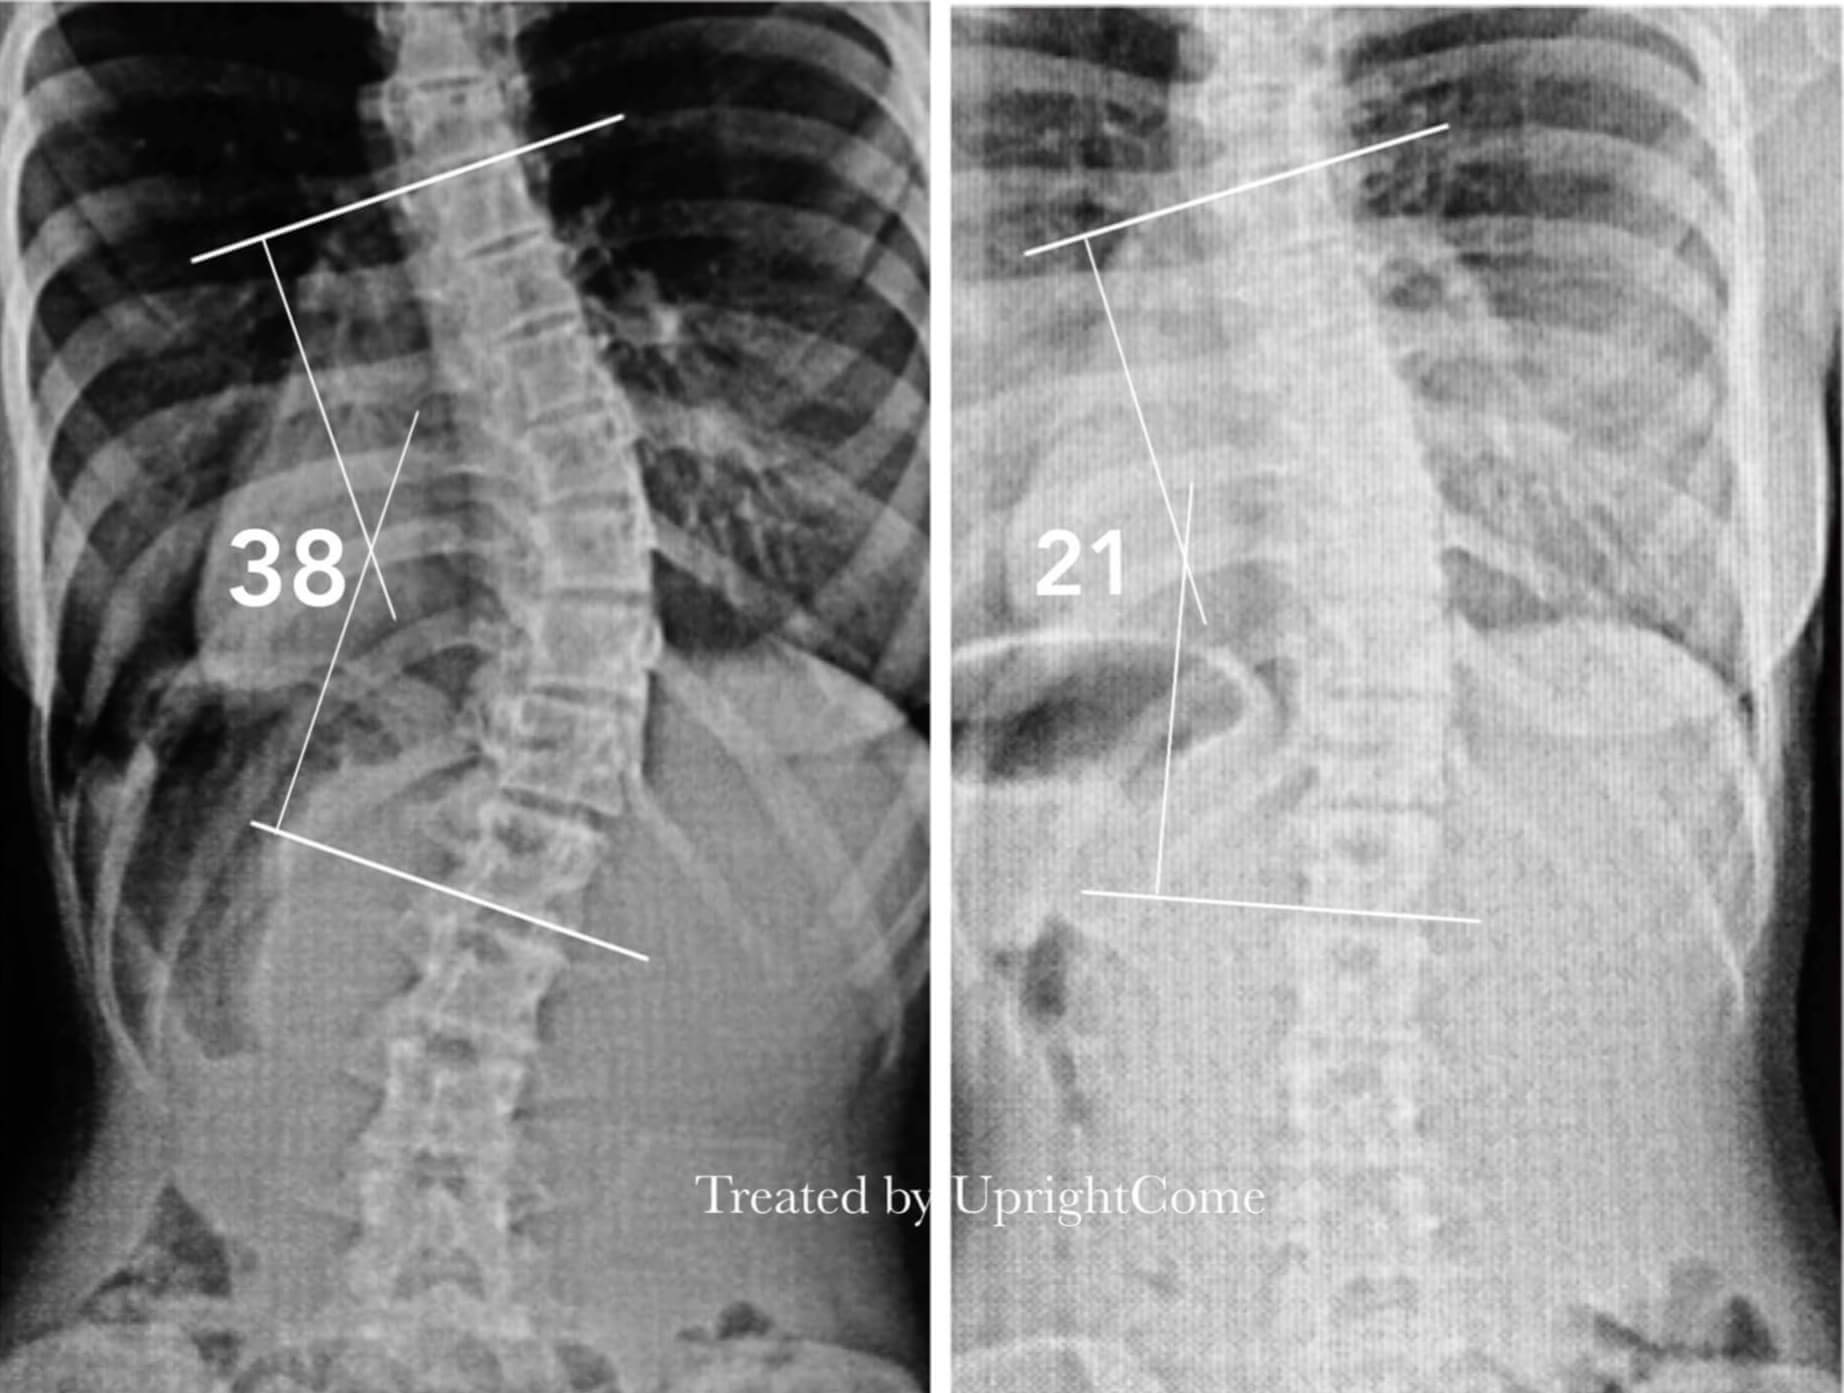

Before/After HOME Before/After X-Ray More Appearance More CLAIM: ABOVE CASES ARE FROM UPRIGHTCOME, UNAUTHORIZED REPUBLISHING OF THE CONTENT IS PROHIBITED. TREATMENT EFFECT DIFFERS FROM PERSON TO PERSON. PROFESSIONAL CONSULTATION AND EVALUATION ARE NECESSARY. «1»